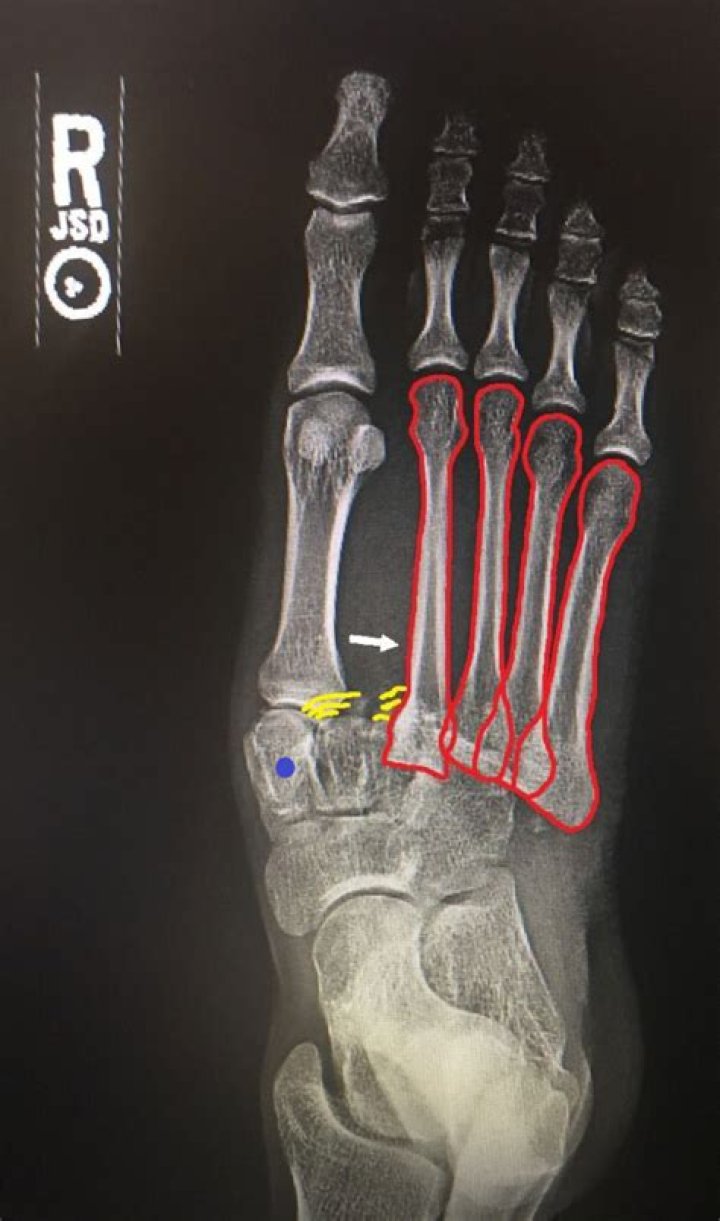

Lisfranc injuries, also called Lisfranc fracture-dislocations, are the most common type of dislocation involving the foot and correspond to the dislocation of the articulation of the tarsus with the metatarsal bases.

The Lisfranc joint is the point at which the metatarsal bones (long bones that lead up to the toes) and the tarsal bones (bones in the arch) connect. The Lisfranc ligament is a tough band of tissue that joins two of these bones. This is important for maintaining proper alignment and strength of the joint.

Clinical presentation Plantar ecchymosis is considered pathognomonic for a Lisfranc injury. Other clinical signs that should trigger clinicians’ suspicions include swelling in the mid-foot and pain during attempted weight-bearing, especially mid-foot pain when walking down stairs.

To determine the type of injury you have in your foot, your doctor will perform a physical exam. While assessing the injured foot for bruising, tenderness, and pain, your doctor will look for bruising at the bottom of your foot, a key indicator of a Lisfranc fracture.